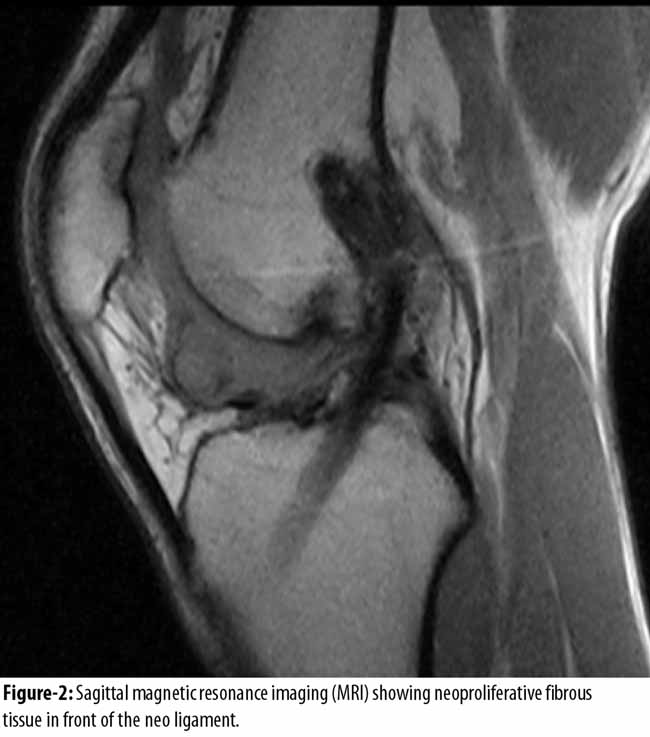

At physical examination, there was no swelling or effusion of the knee. The stability test of knee (Lachman test, Jerk, Pivot Shift, drawer front) were unremarkable and no signs of meniscal tear or cartilage pathology were found. The extension deficit was 7 degrees with pain at terminal extension and deficit of hyperextension. Knee flexion was complete. Magnetic resonance imaging (MRI) was performed which showed slight non-homogeneous signals of the neo-ligament, hyper-intense signals at the external femoral condyle, oedema of the cancellous bone by algodystrophy, degenerative phenomena of both meniscus. Sagittal sections were very suggestive of Cyclops syndrome, with neoproliferative fibrous nodule in front of the neo ligament, producing impingement of the inter-condylar notch (Figure-1 and 2)